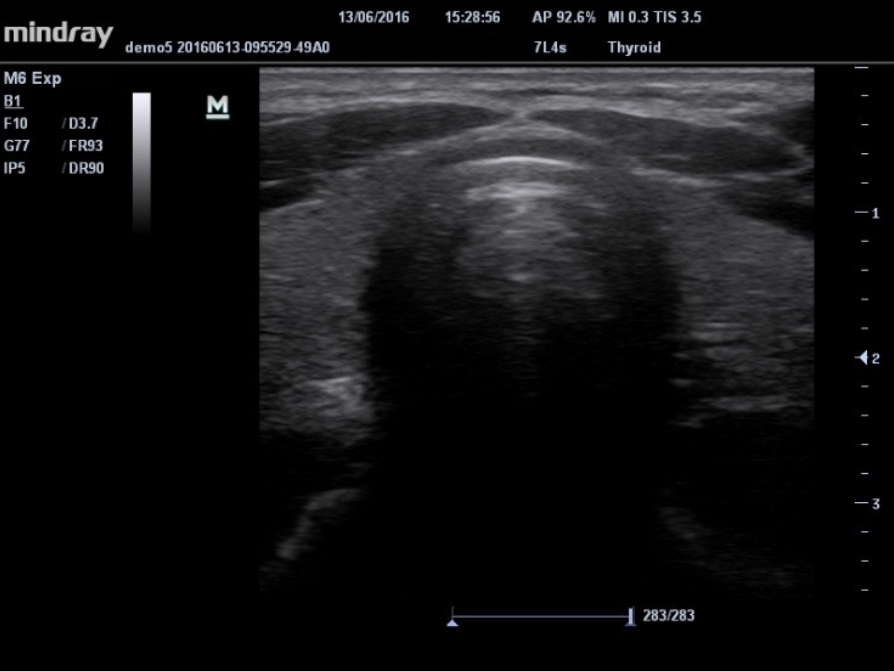

Based on MindrayŌĆÖs latest patented technology, natural touch elastography reduces dependence on user operation technique, improving operatorŌĆÖs reproducibility.

- Higher stiffness sensitivity

- Good stability and reproducibility